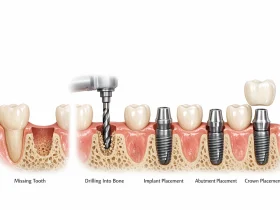

دندان مصنوعی متکی به ایمپلنت (Implant‑Retained Denture)

این پروتز به پایههای ایمپلنت کاشته شده در استخوان فک متصل میشود و ثبات بسیار بالایی دارد.